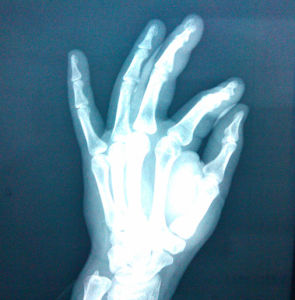

指骨數量

人類共有28塊指骨,其中每隻手各有14塊。